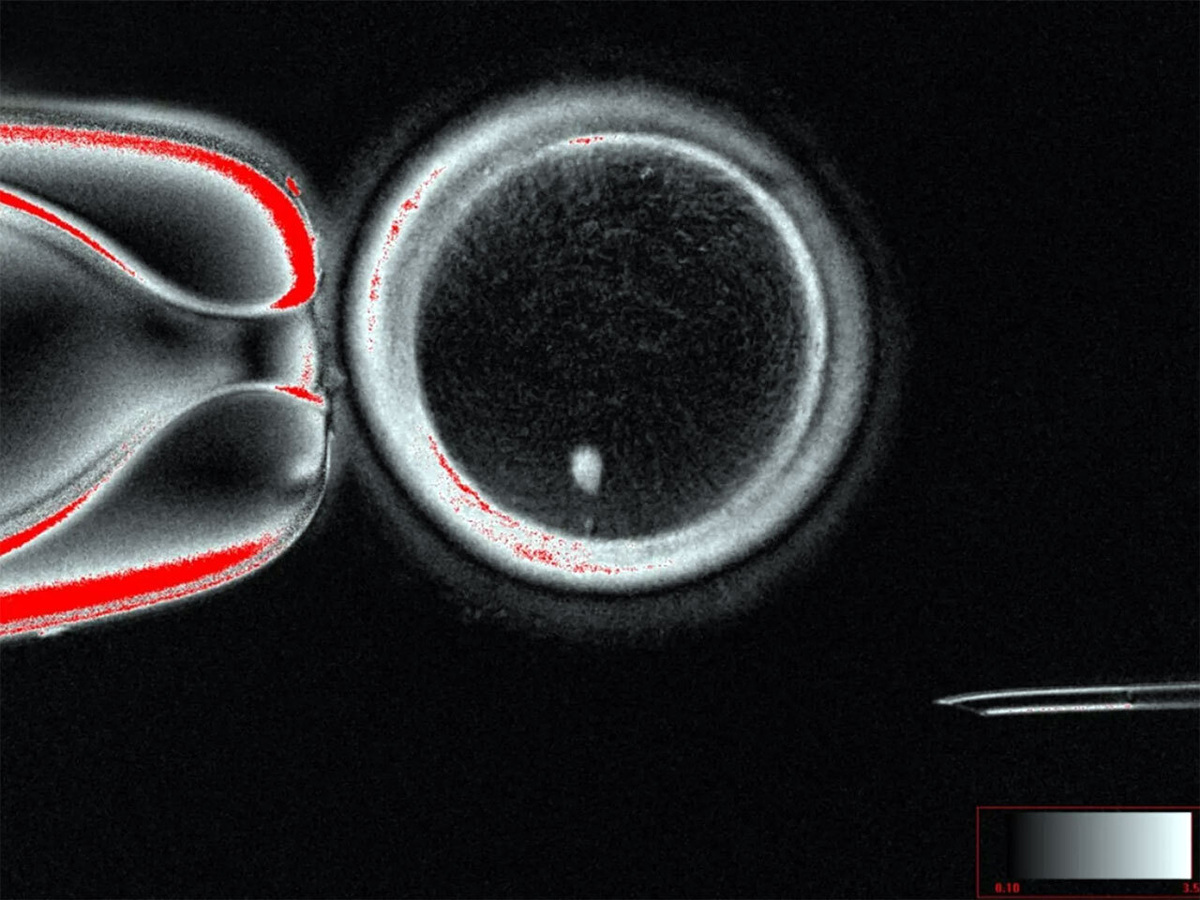

Сначала удалили ядра из сотен яйцеклеток, пожертвованных здоровыми женщинами. Развитие этих гамет остановили аккурат в фазе деления хромосом. Затем в них пересадили ядра фибробластов — клеток кожи, полученных от здоровой женщины-добровольца. На снимках, сделанных под микроскопом, видно, как хромосомы выстраиваются на веретенах — клеточных каркасах для их разделения.

Эти гибридные ооциты оплодотворили спермой здорового донора. По сути, был реализован подход, аналогичный используемому для зачатия детей с использованием митохондриальной ДНК третьего родителя.

В естественных условиях эта инъекция запускает процесс завершения отбора хромосом в яйцеклетке и устранения дубликатов для подготовки к получению новой ДНК от сперматозоида. Но в ооцитах из кожи процесс застопорился: хромосомы выстроились, но так и не завершили разделение. Поэтому исследователи повторили попытку с новой партией оплодотворенных яйцеклеток, используя на этот раз электрические импульсы, помогающие кальцию проникнуть в яйцеклетку — это имитирует естественный сигнал, срабатывающий при контакте сперматозоида с внешней оболочкой яйцеклетки. Ооциты были инкубированы с препаратом, который выводит их из неактивного состояния, в котором они обычно пребывают до оплодотворения.

В ходе серии опытов исследователям наконец удалось получить яйцеклетки, которые уменьшили количество хромосом вдвое, устранив лишние. К концу эксперимента 9% оплодотворенных яйцеклеток превратились в бластоцисты — шарик клеток, который формируется примерно через пять или шесть дней после оплодотворения и который обычно переносят в матку при ЭКО. Экспериментаторы не пытались осуществить такой перенос или поддерживать жизнь бластоцист дольше шести дней.